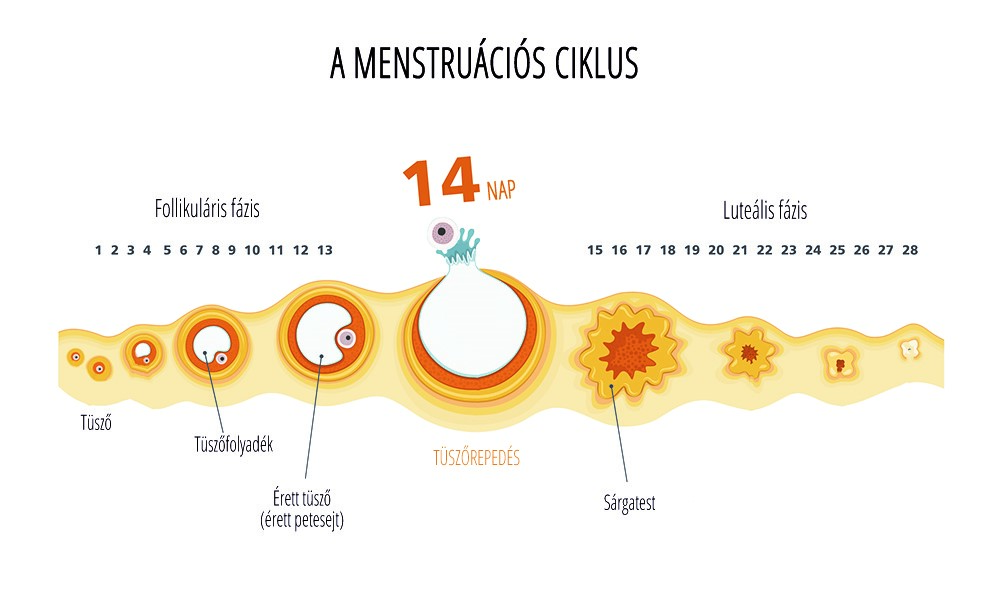

A méh nyálkahártyáját, az úgynevezett endometriális sejtek alkotják, mely, ha nem ágyazódik be embrió, hormonális hatásra leválik, és a nő menstruál.

A méh nyálkahártyáját, az úgynevezett endometriális sejtek alkotják, mely, ha nem ágyazódik be embrió, hormonális hatásra leválik, és a nő menstruál.